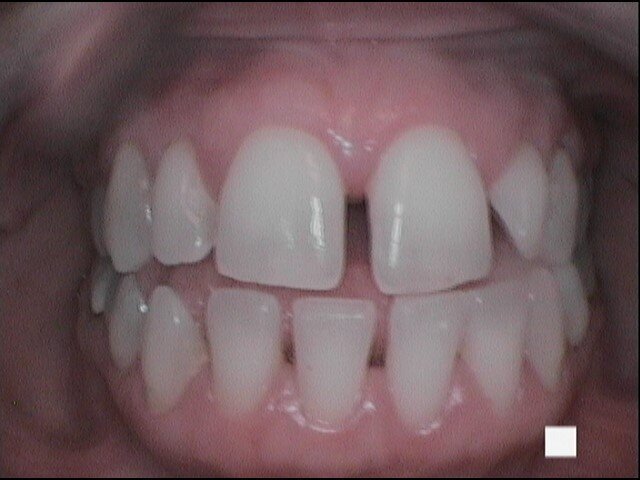

Si presenta alla nostra attenzione un giovane paziente di anni 26, non fumatore, in apparente salute sistemica, in terapia ortodontica con mascherina invisibile lamentando un cattivo odore dell’allineatore, percepito in maniera fastidiosa grazie all’utilizzo obbligato della mascherina per le norme di sicurezza anti-Covid 19. Invitiamo il paziente a rimuovere le mascherine al fine di eseguire un esame obiettivo intra-orale e valutare le condizioni di integrità degli allineatori.

Il paziente ha un buon controllo del biofilm batterico. Viene consigliato il controllo dell’alito attraverso il test organolettico sniff test e il paziente si rassicura poiché non avverte cattivo odore. Chiediamo al paziente in che modo igienizza invece il dispositivo ortodontico e ricordiamo al paziente di aver consigliato l’utilizzo della compressa igienizzante. Il paziente ci riferisce di non aver usato la pastiglia poiché divide l’abitazione con suoi colleghi universitari e non ha piacere di immergere il dispositivo in un bicchiere d’acqua con l’aggiunta della pastiglia igienizzante, poiché lo trova sconveniente e se ne vergogna. Il paziente chiede se può disinfettarla facendola bollire (Figg. 1-9).